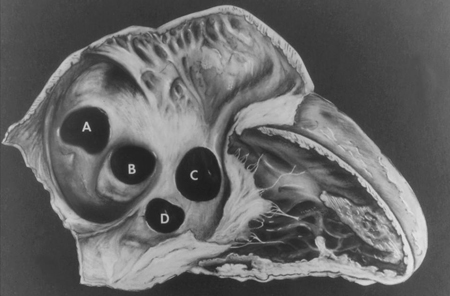

VSD is the most common form of CHD, accounting for 20% of all cases, excluding bicuspid aortic valve and mitral valve prolapse.[20] Subtypes based on location include: peri-membranous (in the area of the membranous septum); outlet (below 1 or both semilunar valves); inlet (inferior to the atrioventricular [AV] valves); and muscular (in the muscular or trabeculated portion of the ventricular septum).[21][Figure caption and citation for the preceding image starts]: Subtypes of ventricular septal defects: (A) outlet; (B) perimembranous; (C) inlet; (D) muscularMayo Clinic Foundation [Citation ends].

Interatrial communications include atrial septal defects (ASDs) and other pre-tricuspid shunts (e.g., sinus venosus defect and unroofed coronary sinus). Pre-tricuspid shunts are defined as the presence of a left-to-right shunt that occur proximal to the right atrio-ventricular valve. As compared to post-tricuspid shunts (such as ventricular septal defect and patent ductus arteriosus), these defects are characterised by low-pressure shunting and varying degree of volume shunting. Pre-tricuspid shunts represent 6% to 10% of all CHDs and have a female-to-male predominance of 2:1.[27] The main types consist of ostium secundum atrial septal defect (60% to 70% of all pre-tricuspid shunts), which occur in the area of the fossa ovalis; ostium primum defect, a form of atrioventricular septal defect (AVSD), in the inferior aspect of the atrial septum; superior and inferior sinus venosus defects (in which the interatrial septum is intact), which are present at the site of the entry of the superior and inferior vena cava, respectively, into the right atrium; unroofed coronary sinus, the least common type.[Figure caption and citation for the preceding image starts]: Subtypes of atrial septal defects: (A) sinus venosus; (B) ostium secundum; (C) ostium primum; (D) unroofed coronary sinusMayo Clinic Foundation [Citation ends].